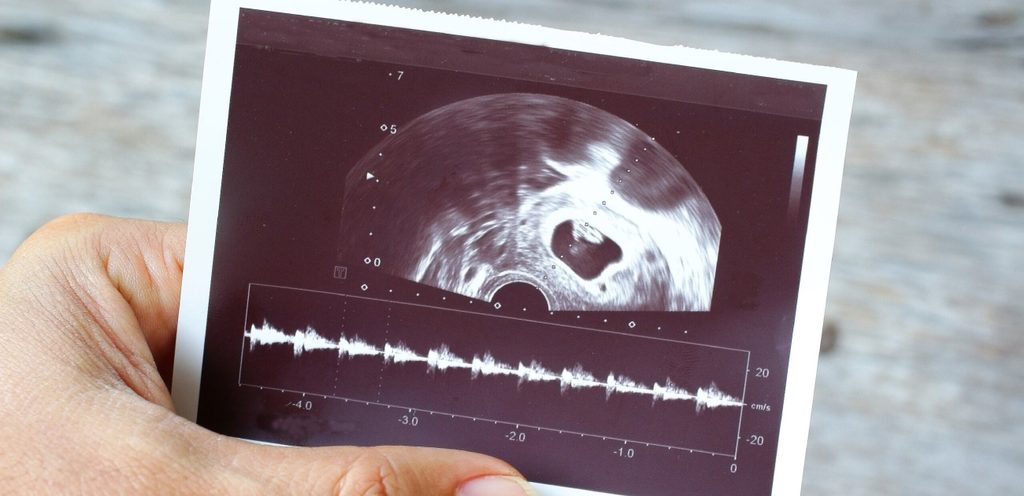

هل يختلف شكل كيس الجنين الذكر في الشهر الثاني عن شكل كيس الجنين الأنثى؟ كيس الحمل هو أول علامة على الحمل المبكر على الموجات فوق الصوتية ويمكن رؤيته بالموجات فوق الصوتية داخل المهبل في حوالي 3-5 أسابيع من الحمل عندما يبلغ متوسط قطر الكيس (MSD) حوالي 2-3 مم في القطر.

وجود كيس صفار البيض: شوهد في حوالي 5.5 أسابيع (دليل لا لبس فيه على كيس الحمل)